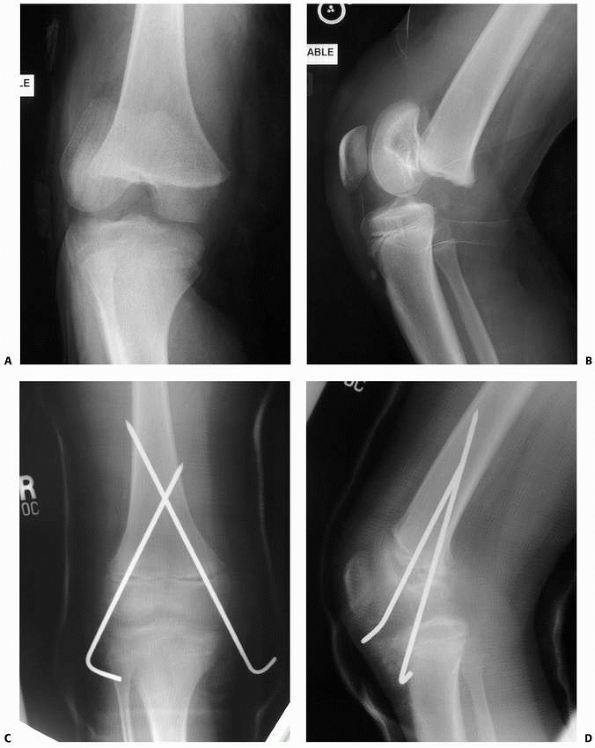

FIGURE 23-7 A. Salter-Harris type I fracture of the distal femur in an 8-year-old. B. Lateral view shows hyperextension. C. Fixation following closed reduction under general anesthesia. Note that pins are widely separated at the fracture site. D. Lateral view of fixation.

|

FIGURE 23-8 A. Salter-Harris type II fracture in a 12-year-old boy. B. Lateral view. C. AP view after closed reduction and fixation. Note that screws function in compression with threads across fracture line. D. Lateral view. E.

Six months after injury, this plain radiograph and clinical picture was suspicious of increased valgus. Note that the radiograph is not centered on the distal physis, and thus the physis is difficult to visualize. |